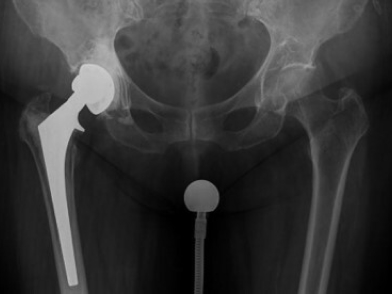

Η διάγνωση της περιπροθετικής χαλαρωσης περιλαμβάνει συνδυασμό κλινικού, απεικονιστικού και μερικές φορές εργαστηριακού ελεγχου. Οι απεικονιστικές μελέτες που χρησιμοποιούνται συνήθως είναι: